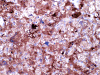

The mass consists of a mixture of spindle cells and clear cells. There is a rich vascular network (Panel A) with sinsusoidal dilatation but no anastomosis of the vascular channels. The endothelial cells appear lean and not protruding into the vascular channel. The clear cells appear to have foamy cytoplasm (̃ in Panel B). The nuclei are hyperchromatic and may appear slighly grooved or lobuated. On immunohistochemistry, the foamy cells are strongly reactive for inhibin (Panel C). These cells are also reactive for S100 protein (Panel D)  and neural specific enolase (Panel E) . No immunoreactivity for epithelial membrane antigen (EMA) is observed (Panel F). The tumor is not immunoreactive for cytokeratin.

Microscopically, hemangioblastomas consist of foamy to clear stromal cells interspersed with endothelium lined vascular channels.  Clear vacuoles within the stromal cells can be stained with Oil red-O or similar stain if applied to frozen sections.  The stromal cells stain strongly for epidermal growth factor receptor (EGFR) and platelet-derived growth receptor factor alpha (PDGF-alpha) 12 and inhibin 13. The stromal cells are typically negative for epithelial membrane antigen (EMA) and cytokeratin 14.  In a small number of cases, the stromal cells express glial fibrillary acidic protein (GFAP)  7, 14 and S100 protein 14. These staining results should be interpreted with case as they may represent entrapped glial cells. The admixed capillaries will stain for with typical endothelial markers (Factor-VIII and others) 15, but the stromal cells are typically negative for the endothelial markers. To this date, the pathogenesis and cell origin of hemangioblastomas is not certain.